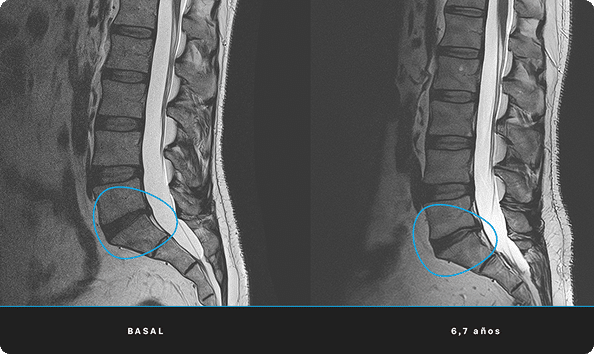

En ITRT hemos demostrado la viabilidad y seguridad de nuestras terapias mediante ensayos clínicos regulados y autorizados por la AEMPS (Agencia Española de Medicamentos y Productos Sanitarios). Una vez superado el ensayo clínico, la AEMPS autoriza el uso del medicamento en pacientes concretos, lo que permite ofrecer tratamientos personalizados con eficacia clínica y capacidad regenerativa demostrada.